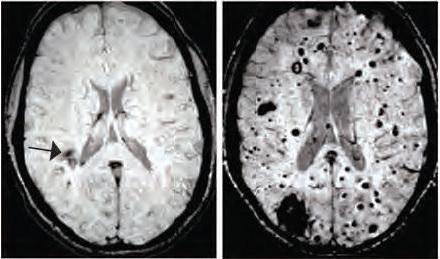

Les malformations caverneuses cérébrales (MCC) - visuel de droite - sont des grappes de vaisseaux sanguins dilatés et à paroi mince qui peuvent entrainer des convulsions ou des accidents vasculaires cérébraux en cas de fuites de sang dans le tissu cérébral environnant.

Des changements dans le microbiote peuvent affecter la progression d'un trouble causé par une mutation génétique : cette équipe de scientifiques de l'Université de Pennsylvanie étudie ici les mécanismes qui provoquent la formation de ces hémangiomes chez des souris génétiquement modifiées et identifient ainsi un lien inattendu avec les bactéries intestinales. Lorsque certaines bactéries sont éliminées, le nombre de lésions diminue en effet considérablement. Les chercheurs ont développé des souris modèles de MCC, les ont transférées dans un nouvel environnement, et constatent que la formation des lésions est presque réduite à zéro - une variabilité dans la formation des lésions également observée chez les humains, où les patients porteurs de la même mutation génétique suivent souvent une évolution pathologique radicalement différente-. Cherchant à cerner la cause de cette variabilité soudaine, les scientifiques remarquent que les quelques souris qui continuent à former des lésions ont développé des abcès bactériens dans leur abdomen. Ces abcès contiennent des bactéries Gram négatives. Lorsque les chercheurs induisent volontairement ces infections bactériennes chez des animaux modèles de MCC, la moitié développe des lésions cérébrales significatives. Ces souris présentent également des abcès dans la rate, ce qui suggère que les bactéries intestinales sont entrées dans la circulation sanguine à partir du site d'abcès de départ. Il y a donc connexion ou propagation de l'intestin, à la rate et au cerveau via le flux sanguin. Et cette propagation entraine la formation de ces lésions vasculaires dans le cerveau.

Mais comment les bactéries dans le sang peuvent-elles influencer le comportement des vaisseaux sanguins dans le cerveau ? Les bactéries Gram négatives produisent des molécules appelées lipopolysaccharides (LPS) qui sont des activateurs puissants de la signalisation immunitaire innée. Lorsque les souris reçoivent des injections de LPS, elles développent des MCC semblables à celles induites par une infection bactérienne. À l'inverse, lorsque les chercheurs " désactivent " 2 récepteurs LPS et TLR4, les souris ne développent plus de lésions MCC. Les chercheurs constatent également que, chez l'Homme, les mutations génétiques provoquant une augmentation de l'expression de TLR4 sont bien associées à un risque accru de formation de MCC. Ainsi, en synthèse, la formation de lésions cérébrales peut être favorisée par des bactéries Gram négatives dans le corps grâce à la signalisation LPS.

Prévenir ces lésions cérébrales en changeant les bactéries du microbiote ? Lorsque les souris modèles de MCC sont élevées ès la naissance dans des conditions exemptes de germes ou sont traitées par antibiotiques afin de " réinitialiser " leur microbiome, le nombre de lésions est considérablement réduit, ce qui confirme que le microbiome intestinal influence la formation de MCC. Et lorsque les chercheurs donnent à ces mêmes souris modèles de MCC un médicament qui bloque spécifiquement TLR4, la formation de ces lésions est considérablement réduite. -De surcroît, ce fameux médicament utilisé pour bloquer le TLR4 a déjà été testé chez les patients pour d'autres affections, et pourrait présenter un potentiel thérapeutique dans le traitement des MCC...-

May 2017 DOI: doi:10.1038/nature22075 Endothelial TLR4 and the microbiome drive cerebral cavernous malformations (Visuel " IRM d'un patient avec mutation favorisant la formation de Malformation caverneuse cérébrale pouvant provoquer une fuite de sang dans les tissus " @Kahn Lab)